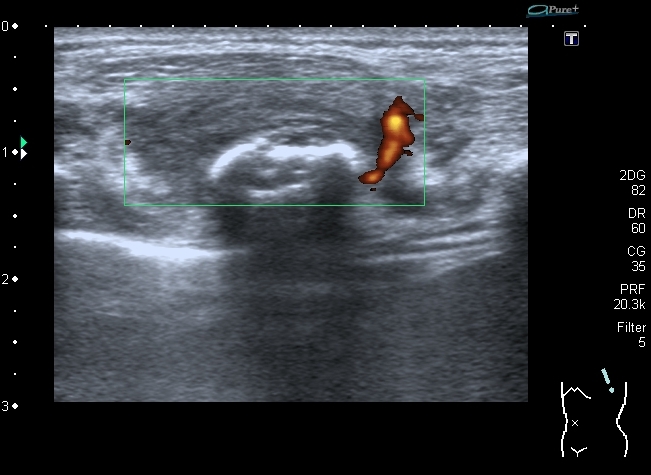

12-years old boy with torax palpable mass 5x3 cm.

Сегодня смотрел мальчика 12 лет, у которого на грудной клетке пальпируется опухоль около 5 см х3 см.

На УЗИ - такая картинка:

образование оттесняет сосуд,  в самом кровоток достоверно не определяется. No bloodflow in mass is detected.